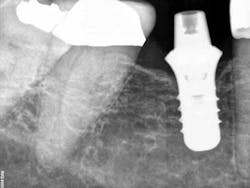

Fig. 1: X-ray of torqued-in prefabricated abutment. The final impression was taken, and a temporary was placed at this visit.

Fig. 2: X-ray of crown try-in two weeks after initial visit. No cement had been used at this point in the appointment. However, if you look at the distal of the implant, there is residual cement. This means that the cement came from the cementation of the temporary.